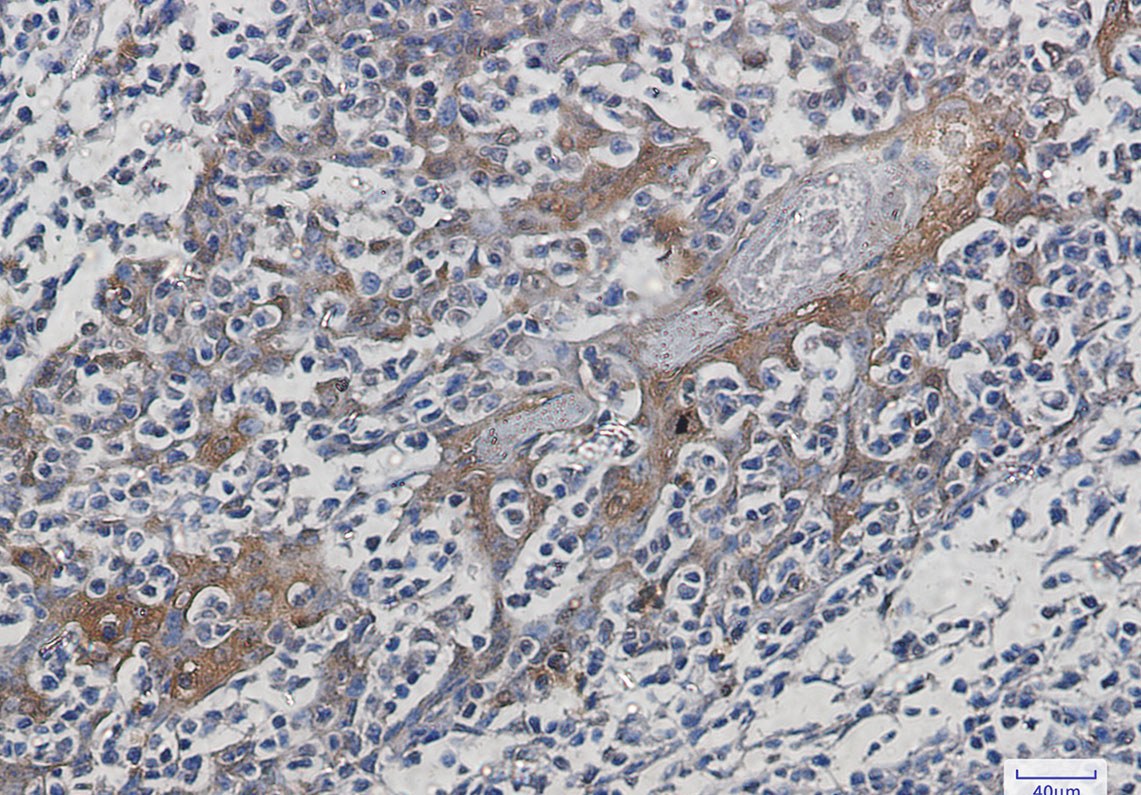

IHC 1/50-1/100 Human,Mouse,Rat

Hsp70 antibodies are widely used in techniques like Western blot, immunohistochemistry, and immunofluorescence to detect Hsp70 expression, localization, and interactions. These antibodies help investigate roles of Hsp70 in diseases, including cancer (where Hsp70 is often overexpressed to support tumor survival), neurodegenerative disorders (e.g., Alzheimer’s and Parkinson’s diseases linked to protein misfolding), and infections (pathogens exploit host Hsp70 for replication). Researchers also employ them to study Hsp70’s dual role in apoptosis—either promoting cell death or survival, depending on context.